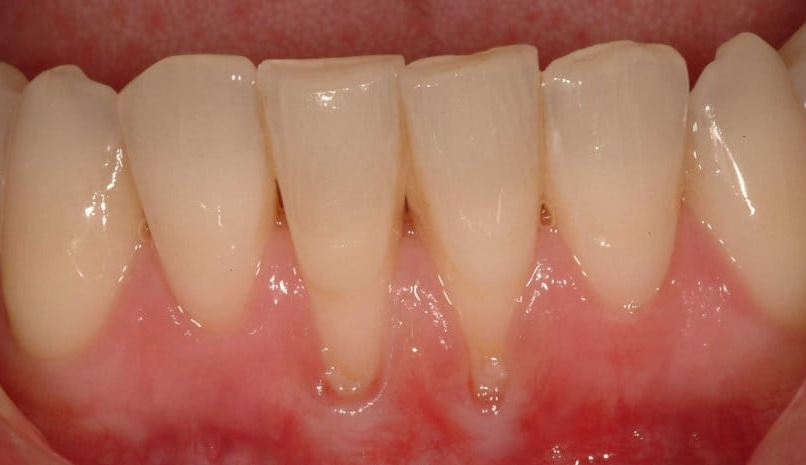

잇몸 내려앉음은 치아를 둘러싸고 있는 잇몸 조직이 치아에서 멀어지면서 내려가는 현상입니다. 이로 인해 치아의 뿌리가 노출되며, 이는 다양한 치아 문제를 유발할 수 있습니다. 잇몸 내려앉음은 단순한 미용 문제를 넘어서, 치아의 건강에도 큰 영향을 미칠 수 있습니다.

잇몸 내려앉음의 증상은 다음과 같습니다. 첫째, 잇몸이 붓거나 피가 나는 경우가 많습니다. 둘째, 치아가 길어 보이는 느낌이 들 수 있습니다. 셋째, 찬 음식을 먹을 때 이가 시리거나 통증이 느껴질 수 있습니다. 이러한 증상이 나타나면 즉시 치과를 방문하는 것이 중요합니다.